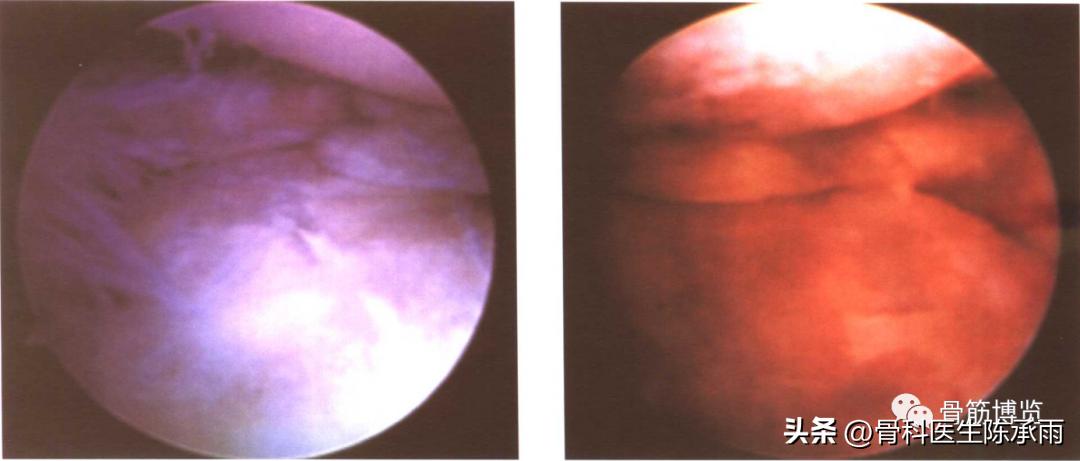

(七)退行性变性撕裂

因为这种撕裂表现为明显的不规则性,往往见于老年骨性关节炎的病人。我们认为它不是一种单纯的损伤,而是由于关节软骨退行性改变后,股骨髁的半月板区骨及软骨与相对应的胫骨平台表面软骨间,长期反复的磨损所致。在有的病人,甚至镜下也不能观察到完整的半月板形态,仅可见残留的参差不齐的半月板边缘。而这时的关节软骨已大部分剥脱,仅剩淡红色的骨床以及表面的部分软骨岛。